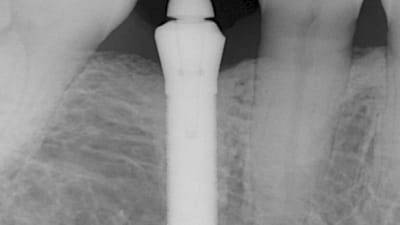

Online Only Implantology Online Only Repair of a Non-Retentive Crown Over a Press-Fit Implant Placed 30 Years Prior By Leonor Limao Oliveira, DDS, Reem A. Alghamdi, DDS, Sang-Choon Cho, DDSDDS, Stuart J. Froum, DDS, Vatsal Jaipuria, BDS July 15, 2022 12 min read